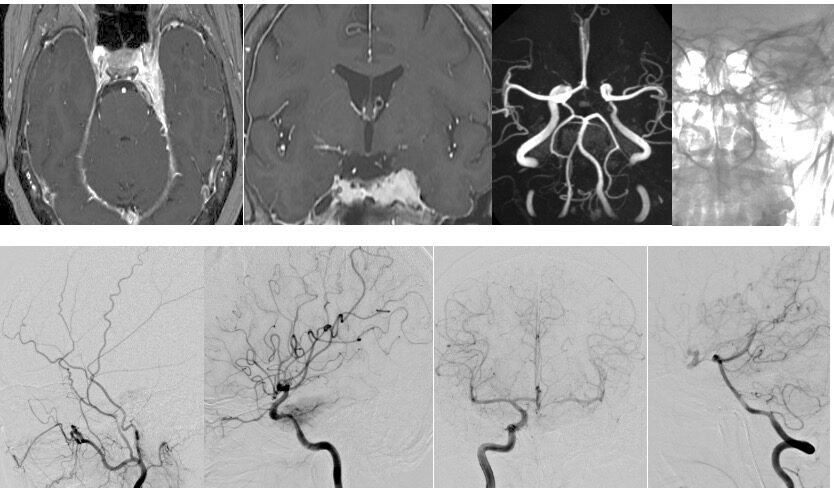

左海綿静脈洞内髄膜腫(複視)に対して、現在のスタンダードは放射線治療になりつつありますが、これも長期制御が困難なので、今回はBTOで左内頸動脈閉塞による血管内腫瘍塞栓を行う計画としました。それに先立ち、BTO時のStump <50mHgであったためSTA-MCAバイパスを行いました。